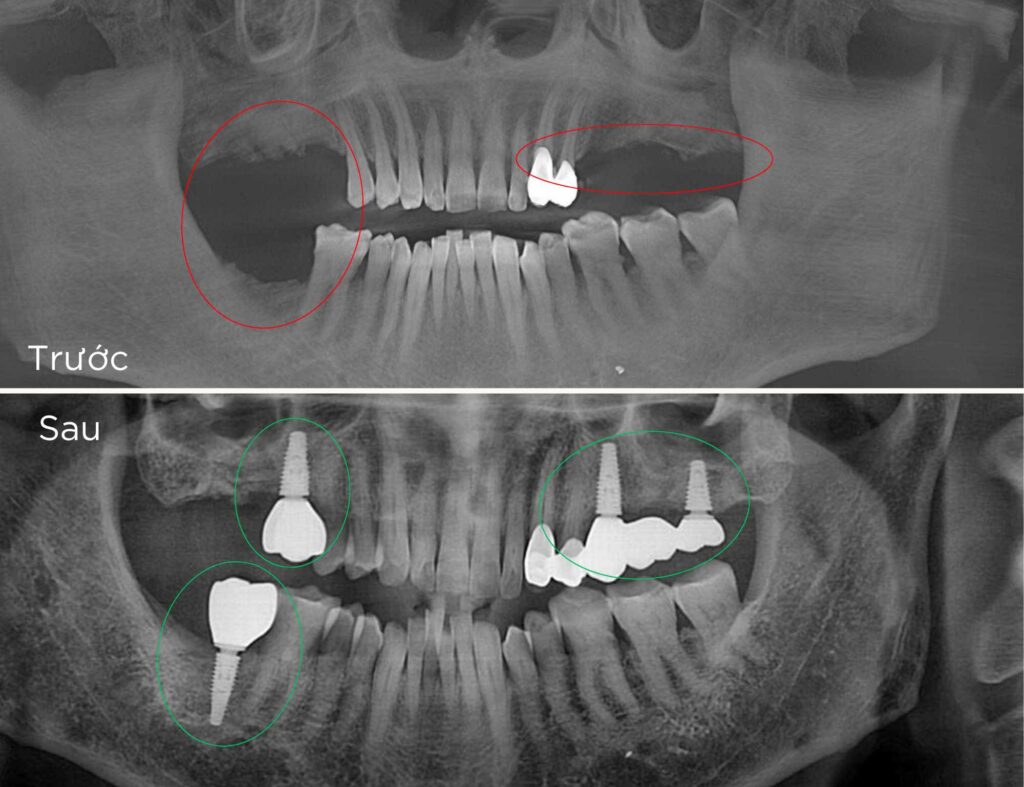

Trồng Implant vài răng

Trồng răng Implant vài răng

để phục hồi răng và tái tạo hình dáng của các răng đã mất. Là giải pháp tối ưu cho những người mất từ hai răng trở lên, giúp khôi phục khả năng ăn nhai, cải thiện thẩm mỹ và ngăn ngừa các vấn đề do mất răng gây ra, như tiêu xương hàm hay lệch khớp cắn.